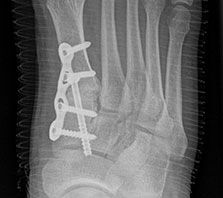

Röntgen

Standard ist die belastete Röntgenaufnahme des Fußes dorso-plantar und seitlich. Günstig ist eine Röhrenkippung von 10°-20°, um die Gelenke der Lisfranc-Linie einsehen zu können.

Ergänzend kann eine Schrägaufnahme hilfreich sein. Bei Metatarsalgien oder Pathologien der Sesambeine liefert die Sprinteraufnahme zusätzliche Informationen. Bei einer Pes planovalgus Fehlstellung wird ergänzend ein Saltzman view durchgeführt.

Bezüglich der Operationstechniken wird von früher häufig durchgeführten alleinigen Weich­teileingriffen am Großzehengrundgelenk aufgrund hoher Rezidivraten abgeraten 15. Die Operation nach Mc Bride mit lateralem Release, Exzision des lateralen Sesambeins, Abtragen der Pseudoexostose, Sehnenetransfer des M. adductor hallucis und mediale Kapselraffung zeigte unbefriedigende Mittel- und Langzeitergebnisse 16. Die Cerclage fibreux (mediale Kapselraffung) und das laterale Kapselrelease wird heute in Kombination mit einem knöchernen Eingriff angewendet. Bezüglich des Einsatzes von minimalinvasiven Operations­techniken vor Wachstumsabschluss liegen bisher keine Daten vor. Alle Osteotomien lassen sich nach Bedarf miteinander kombinieren. Es ist darauf zu achten, dass Osteotomien keine offenen Wachstumsfugen verletzen.

• medial aufklappende Cuneiforme I Osteotomie 1522

• Nach Schluss der Wachstumsfugen: TMT I Arthrodese nach Lapidus 2425